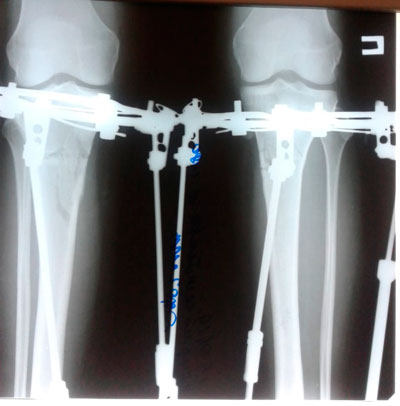

Исходник - 39 лет.

Дата операции - 03.06.2019г.

IMG_3432-01-06-19-11-56.JPG

IMG_3427-01-06-19-11-56.JPG